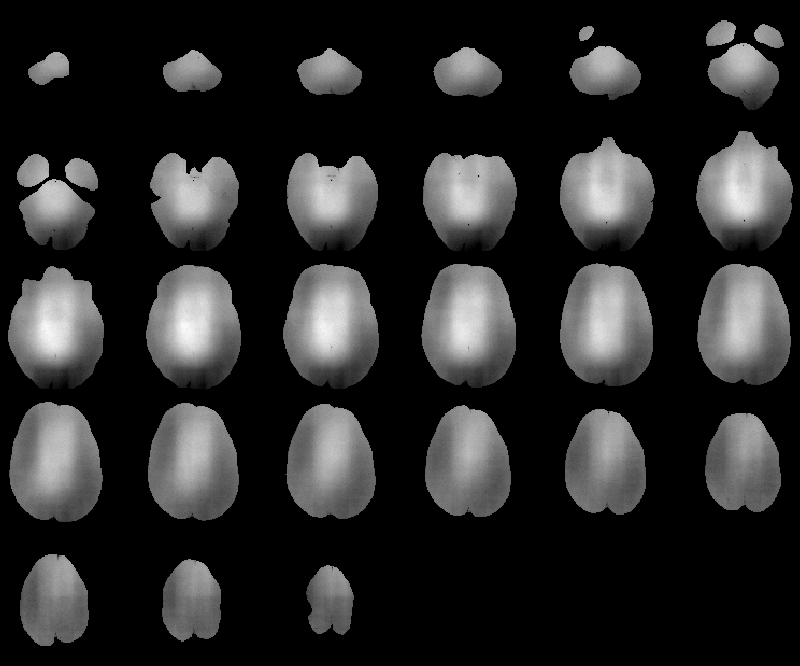

The RF inhomogeneity detected in Data Set 2 by the Correct Intensity process is displayed in Figure 8.29. Slice 16 is highlighted in Figure 8.30.

Figure 8.29: RF inhomogeneity detected in

MRI Data Set 2.

Figure 8.30: Slice 16 of MRI Data Set 2 (a) before

and (b) after RF correction.